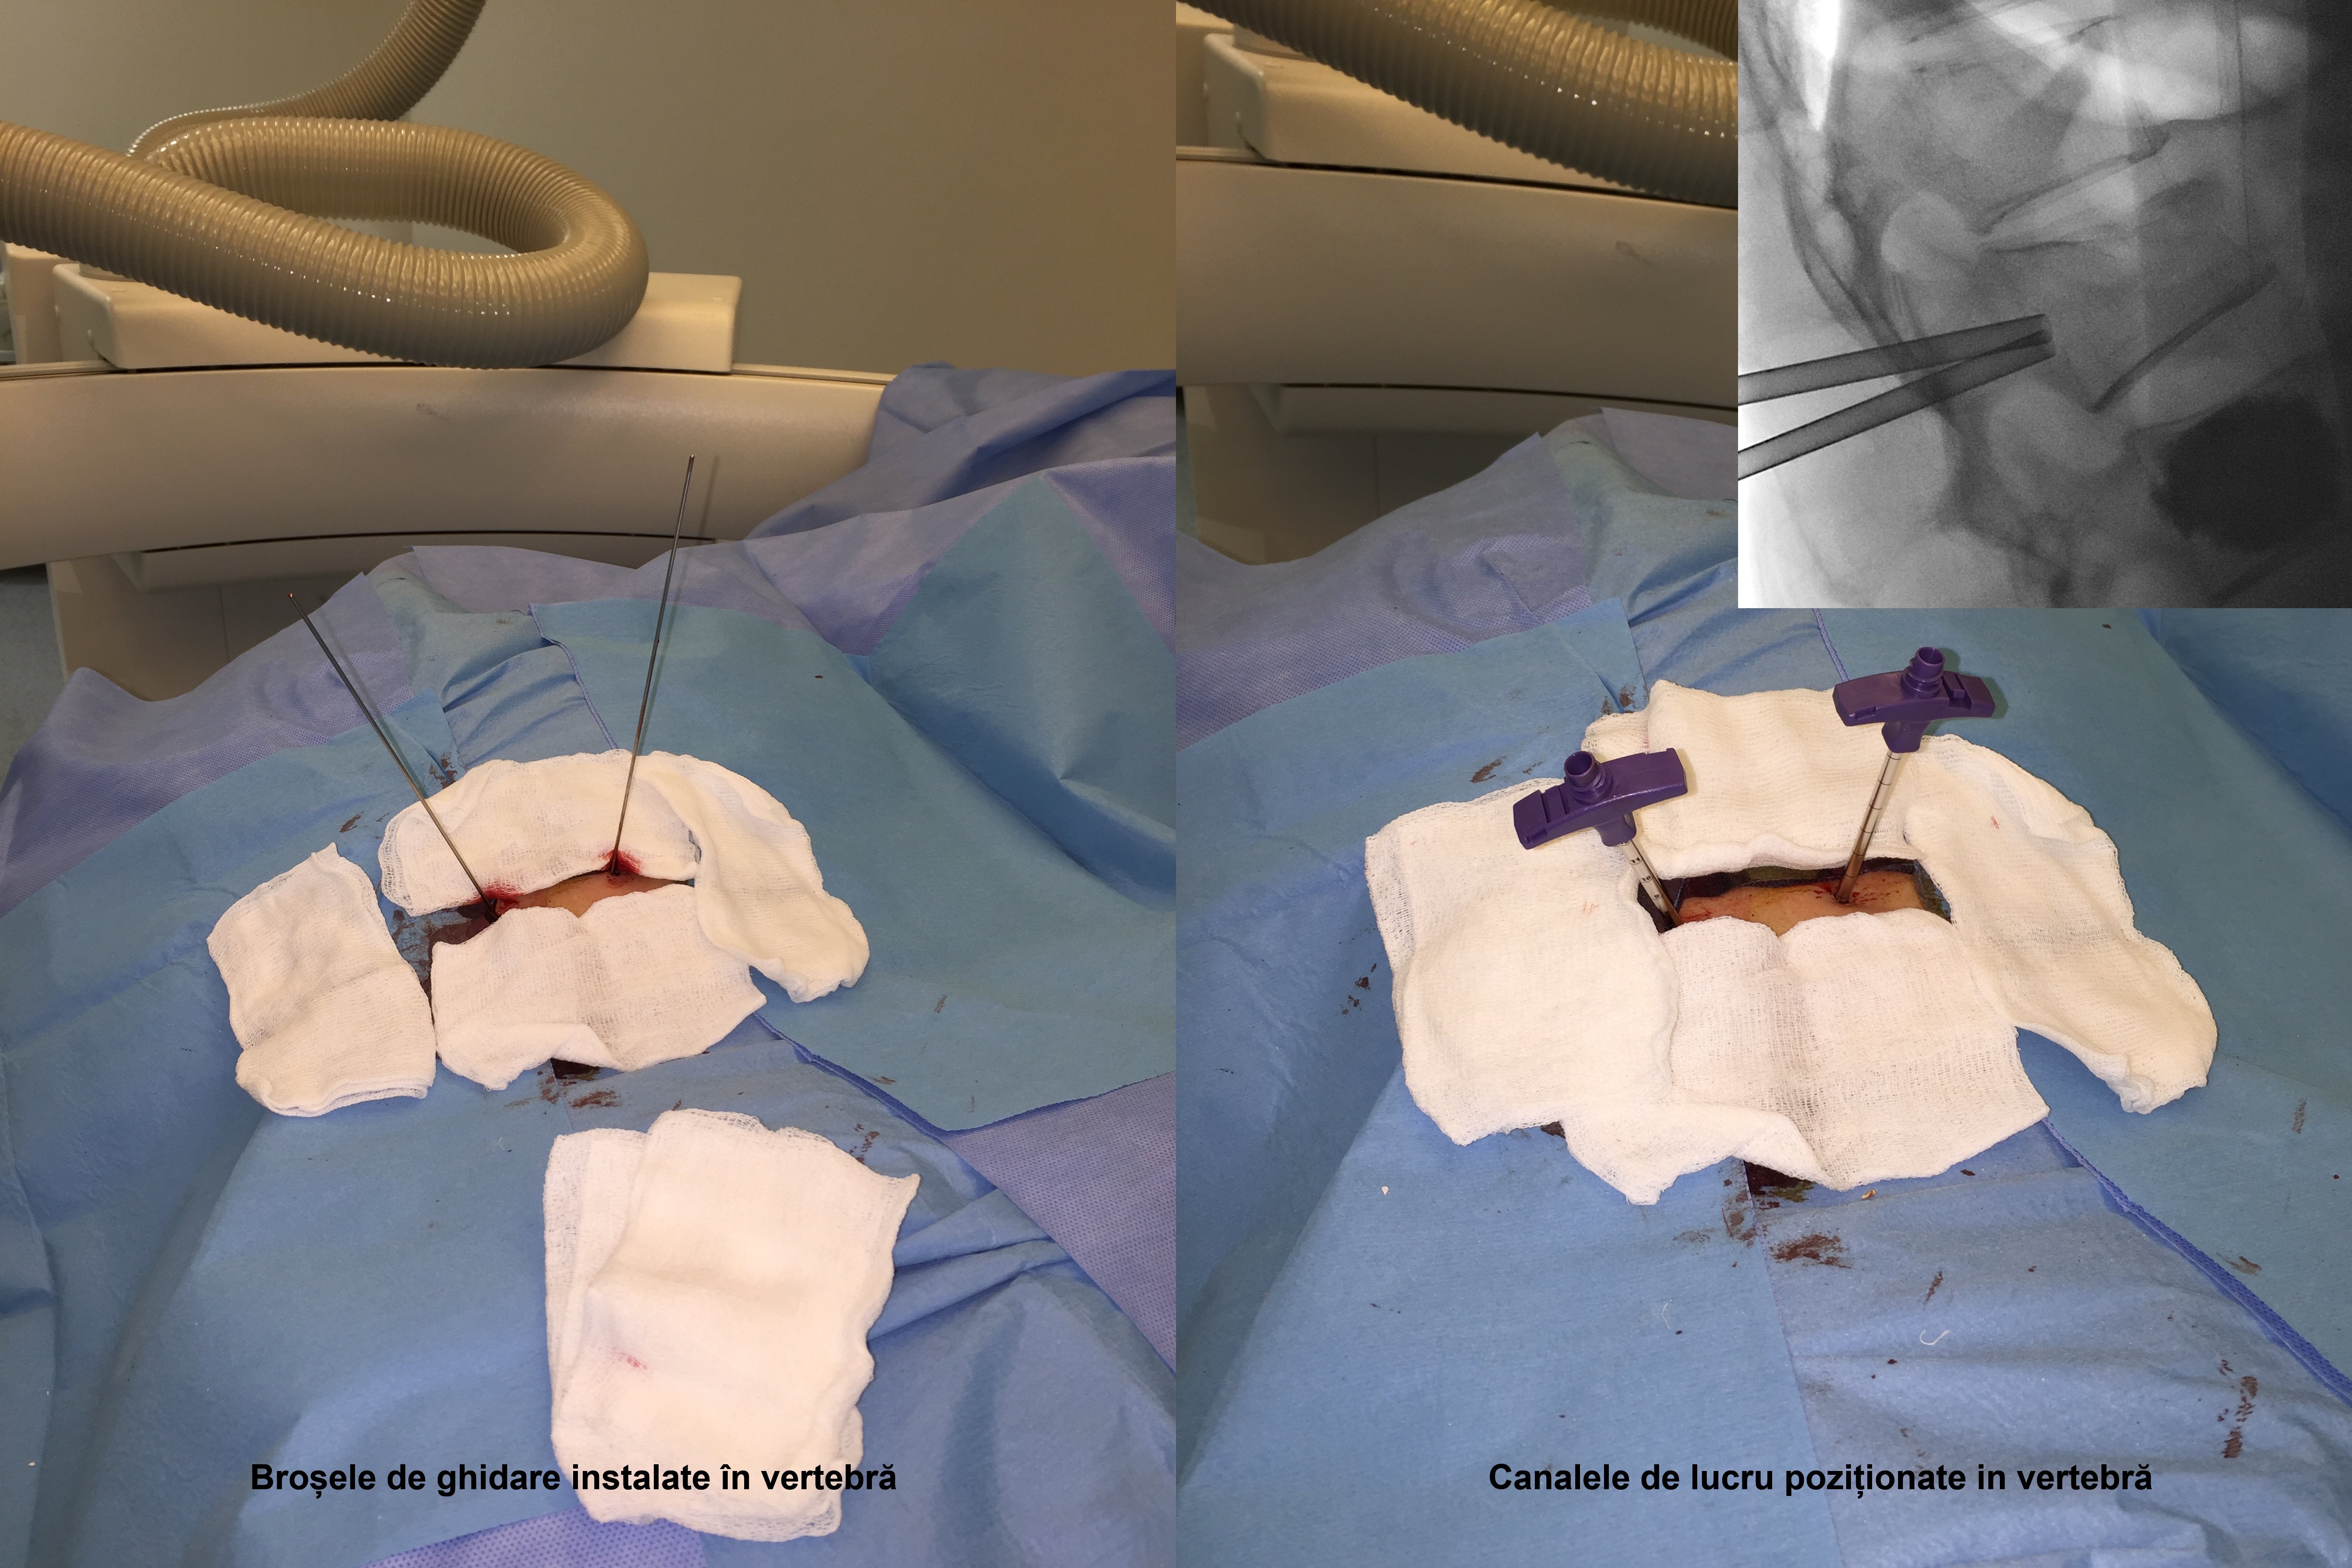

Kyfoplastia reprezintă o procedură minim invazivă în timpul căreia chirurgul introduce în corpul vertebral un tub cu un balon expandabil. Sub control fluoroscopic are loc expansionarea balonului în corpul vertebral, cu restabilirea înălţimii corpului vertebral şi corijarea diformităţii kifotice. Ulterior, în cavitatea formată de balon, se introduce cimentul acrilic, ceea ce contribuie la consolidarea vertebrei.

Realizarea intervenţiilor percutanate de acest tip presupune utilizarea unui fluoroscop intraoperatoriu, cu scopul de a reduce la minim complicaţiile (cum ar fi, leziuni ale structurilor nervoase, scurgerea cimentului extracorporeal, embolii venoase, etc.). În cazul pacientei noastre, a fost utilizată instalaţia de Angiografie tridimensională (3D) Siemens ”Artis Zee”, disponibil în sala de operaţii Hybrid a Spitalului Clinic Republican, care asigură o calitate excepţională a imaginilor intraoperatorii.

Vertebroplastia percutană a corpului LII a fost executată prin abord unilateral transpedicular pe stânga, în timp ce Kyfoplastia cu baloane expandabile a corpului vertebral LI - prin abord bilateral transpedicular pe stânga.